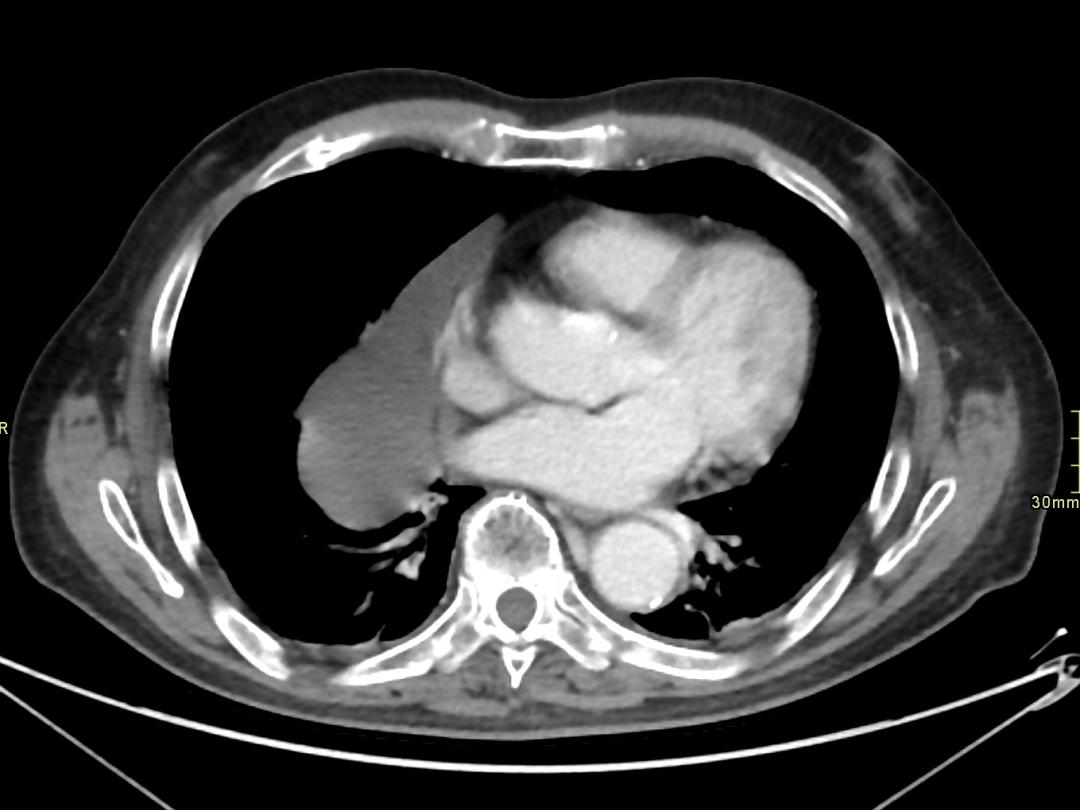

Een 80-jarige man, bekend met cognitieve stoornissen na ernstig hersenletsel, werd op de polikliniek Geriatrie gezien in verband met achteruitgang van de cognitie. Hij was enkele weken eerder op de SEH geweest in verband een influenza A-infectie. Op de longfoto waren toen infiltratieve afwijkingen gezien, maar ook een bolronde afwijking. Op de polikliniek had hij geen klachten meer van kortademigheid, slikstoornissen of hoesten. De bloeddruk (117/67 mmHg), polsfrequentie (83/min) en zuurstofsaturatie (100%) waren niet afwijkend. Ook verder lichamelijk onderzoek bracht geen afwijkingen aan het licht. Als verklaring voor de bolronde afwijking dacht de geriater aan een restafwijking na de…